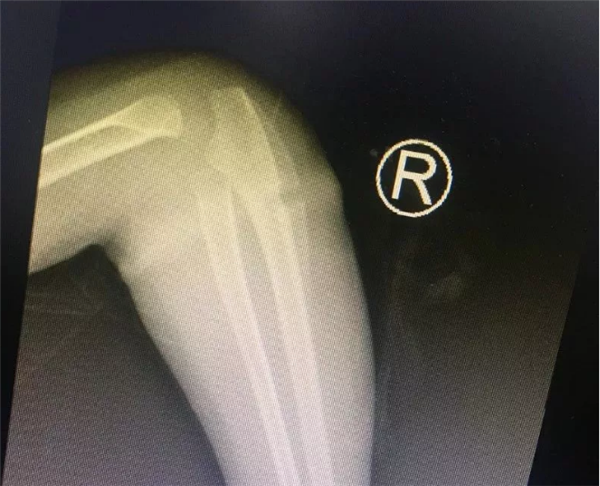

几天前,困扰安徽临泉乐乐一家人半年之久的手臂“圆环”事件终于真相大白了。难以想象的是一根很普通的橡皮筋竟然偷偷“长”进孩子的肉里!最终,浙大儿院湖滨院区骨科叶文松副主任在孩子的手臂中找出橡皮筋,解决了孩子手臂肿胀的痛苦。

4岁的乐乐长期跟着爷爷奶奶生活,不知从什么时候开始,右侧手臂莫名其妙长了一圈“圆环”。最初家里人没有在意这个“圆环”,哪知道乐乐的右前臂一天比一天更红肿。2018年过年后,乐乐手臂严重肿胀,疼痛,而且手指活动受限。看到孩子右前臂比左前臂足足肿大了一圈,这时乐乐的家人才担心起来。

叶主任看了乐乐的手臂,告诉孩子的家长,“圆环”很可能是橡皮筋导致的。虽然乐乐父母不大相信,还是听从叶主任的建议,让乐乐入院了。没多久,入院后B超检查结果出来了,也证实了叶主任的诊断是正确的。

有了明确的诊断,骨科各位医生开始为乐乐手术。这个手术并不难,无影灯下,历经半小时就将“圆环”擒拿归案,把长在肉里的环形橡皮筋取了出来,彻底解决了乐乐的病痛。